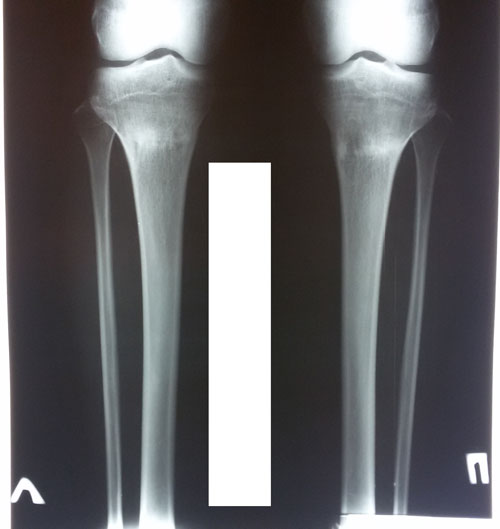

Рентген контроль в 2 месяца с момента снятия аппаратов.

Здравствуйте, А.! По рентгену всё отлично! Ограничений в нагрузках нет, каблуки разрешены. Для разработки суставов - массаж, гимнастика, очень хорошо помогает боди балет. Хорошие результаты после его занятий, наши пациентки оценили.